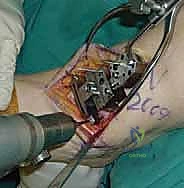

4. وضع أدلة القطع (Jig Placement and Alignment)

تعتمد دقة الجراحة على المحاذاة الصحيحة. يتم استخدام أجهزة توجيه متطورة (Jigs) تثبت على عظمة الساق باستخدام دبابيس معدنية. يتم التحقق من صحة الزوايا والمحاور باستخدام جهاز الأشعة السينية المباشر داخل غرفة العمليات (C-arm Fluoroscopy). يضمن الدكتور هطيف أن يكون القطع موازياً للأرض تماماً عند وقوف المريض.

5. القطع العظمي الظنبوبي (Tibial Bone Cut)

باستخدام منشار جراحي دقيق التذبذب، يتم إزالة شريحة رقيقة جداً (بضعة مليمترات) من السطح السفلي التالف لعظمة الظنبوب. يتم القطع بحذر شديد لتجنب إصابة الأوتار الخلفية أو الأوعية الدموية.

6. القطع العظمي الكاحلي (Talar Bone Cut)

بشكل مشابه، يتم توجيه دليل القطع نحو عظمة الكاحل (Talus) وإزالة السطح الغضروفي التالف وت